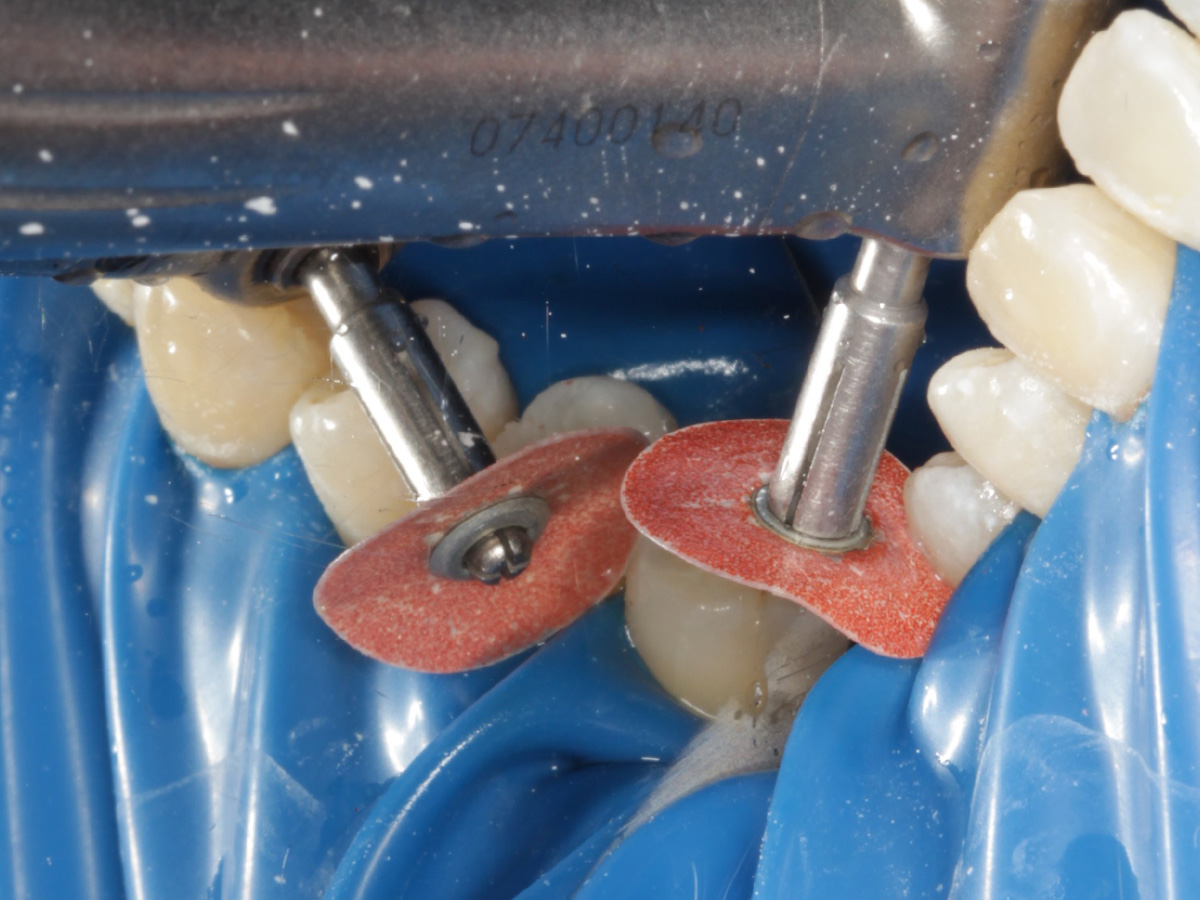

Abbildung 16

Überschussentfernung/ „Anpolieren“ u.a. trocken mit Sandpapierscheibe

Abbildung 17

Zahnseidenkontrolle: kein Überschuss, satter Kontaktpunkt